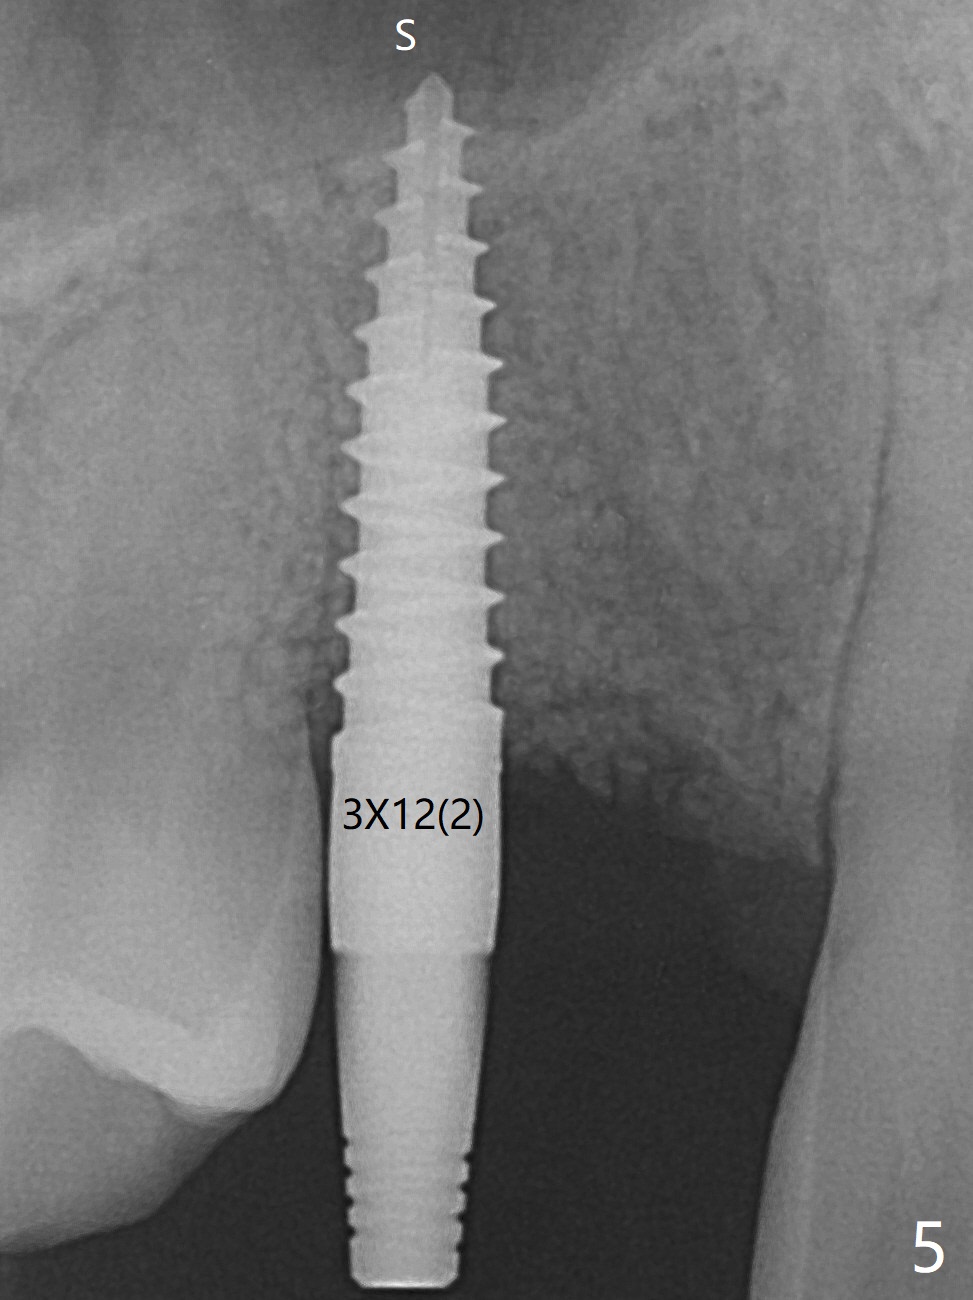

右上尖牙植体拔除,植骨后6个月,切开显示不可吸收膜覆盖的牙槽骨尚饱满(图一),不可吸收膜下面形成一个膜(可能是骨膜,图二:M),在导板指导下,植入3x12(2)毫米一段式植体,颊侧(图三),腭侧(图四)骨下,稍微穿过窦底(图五),植体覆盖粘性骨粉(图六)和PRF膜后,4-0 PGA缝合。伤口有一定张力,使用牙周敷料。术后10天没有疼痛(就没有骨坏死),由于基台存在,牙周敷料没有脱落迹象(图七),也没有撤除。敷料术后13天脱落,伤口好像正常愈合(图八)。由于病人即将回外州上学,提前取模。他喜欢左边牙冠修复形式(牙冠覆盖牙龈),而我们想让牙冠位于牙龈舌侧(图十:T(临时牙冠))。